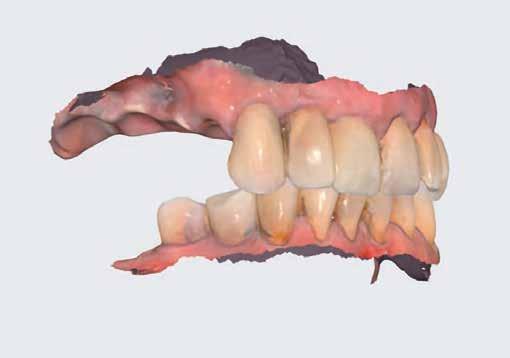

A TELJES FELSŐ ÁLLCSONT

REHABILITÁCIÓJA DIGITÁLIS MUNKAFOLYAMATTAL

A teljes foghiány egy olyan irreverzibilis állapot, amely a szájüregi egészséget érintő betegségteher ismert mutatója. [1] A foghiány jelentősen befolyásolja mind a szájüregi, mind az általános egészségi állapotot, valamint az életminőséget. [2] A teljes állcsont implantátumokkal történő rehabilitációja megbízható és kiszámítható kezelési lehetőséget jelent foghiányos esetekben. [3] Az új fejlesztések, mint például a virtuális tervezés, ideális lehetőséget teremtenek az implantátum behelyezéséhez, mégpedig pontos protetikai pozícióhoz igazodva, és minimalizálják az intraoperatív traumát, illetve a beavatkozás időtartamát. [4]

Az alábbi esetismertetés egy 70 éves, rágási nehézségekkel küzdő beteg sikeres kezelését mutatja be. A hat Straumann Bone Level Tapered (BLT) implantátummal és digitális munkafolyamattal végzett, teljes felső állcsont-rehabilitációval a páciens életminőségét jelentős mértékben javítottuk és teljes mértékben kielégítettük az elvárásait.

Kiindulási állapot

Az egészséges, gyógyszert nem szedő, allergiában nem szenvedő, nem dohányzó páciens rágási nehézségei miatt

kereste fel rendelőnket. Ezen felül folyamatos halitózisra is panaszkodott. A páciens szerette volna visszaszerezni a korábbi rágási képességét és helyreállítani az életminőségét, illetve az önbizalmát is.

Az extraorális vizsgálat során alacsony mosolyvonalra derült fény; az intraorális vizsgálat során pedig egy kivehető híd volt látható a 13-as fogtól a 23-as fogig, amely nem megfelelően illeszkedett és cserére szorult. A jobb felső bölcsességfog kivételével az összes fog mobilis volt a felső állcsonton. Generalizált gingivitis, szondázási ínyvérzés és caries is kimutatható volt (1. ábra). A röntgenfelvétel súlyos csontveszteséget mutatott a bal felső kvadránsban, valamint cariest és periapikális elváltozásokat a felső fogak esetében (2. ábra).

Teljes felső lenyomatot vettünk nyitott kanalas lenyomatvételi elemekkel és poliéter lenyomatanyaggal (Impregum, 3M ESPE). Néhány óra elteltével kofferdamot helyeztünk az ideiglenes felépítmények köré, hogy óvjuk a friss műtéti területet. Ezután a korábban elkészített, műgyanta alapú anyagból készült ideiglenes fogpótlást a helyére rögzítettük (10–12. ábra).